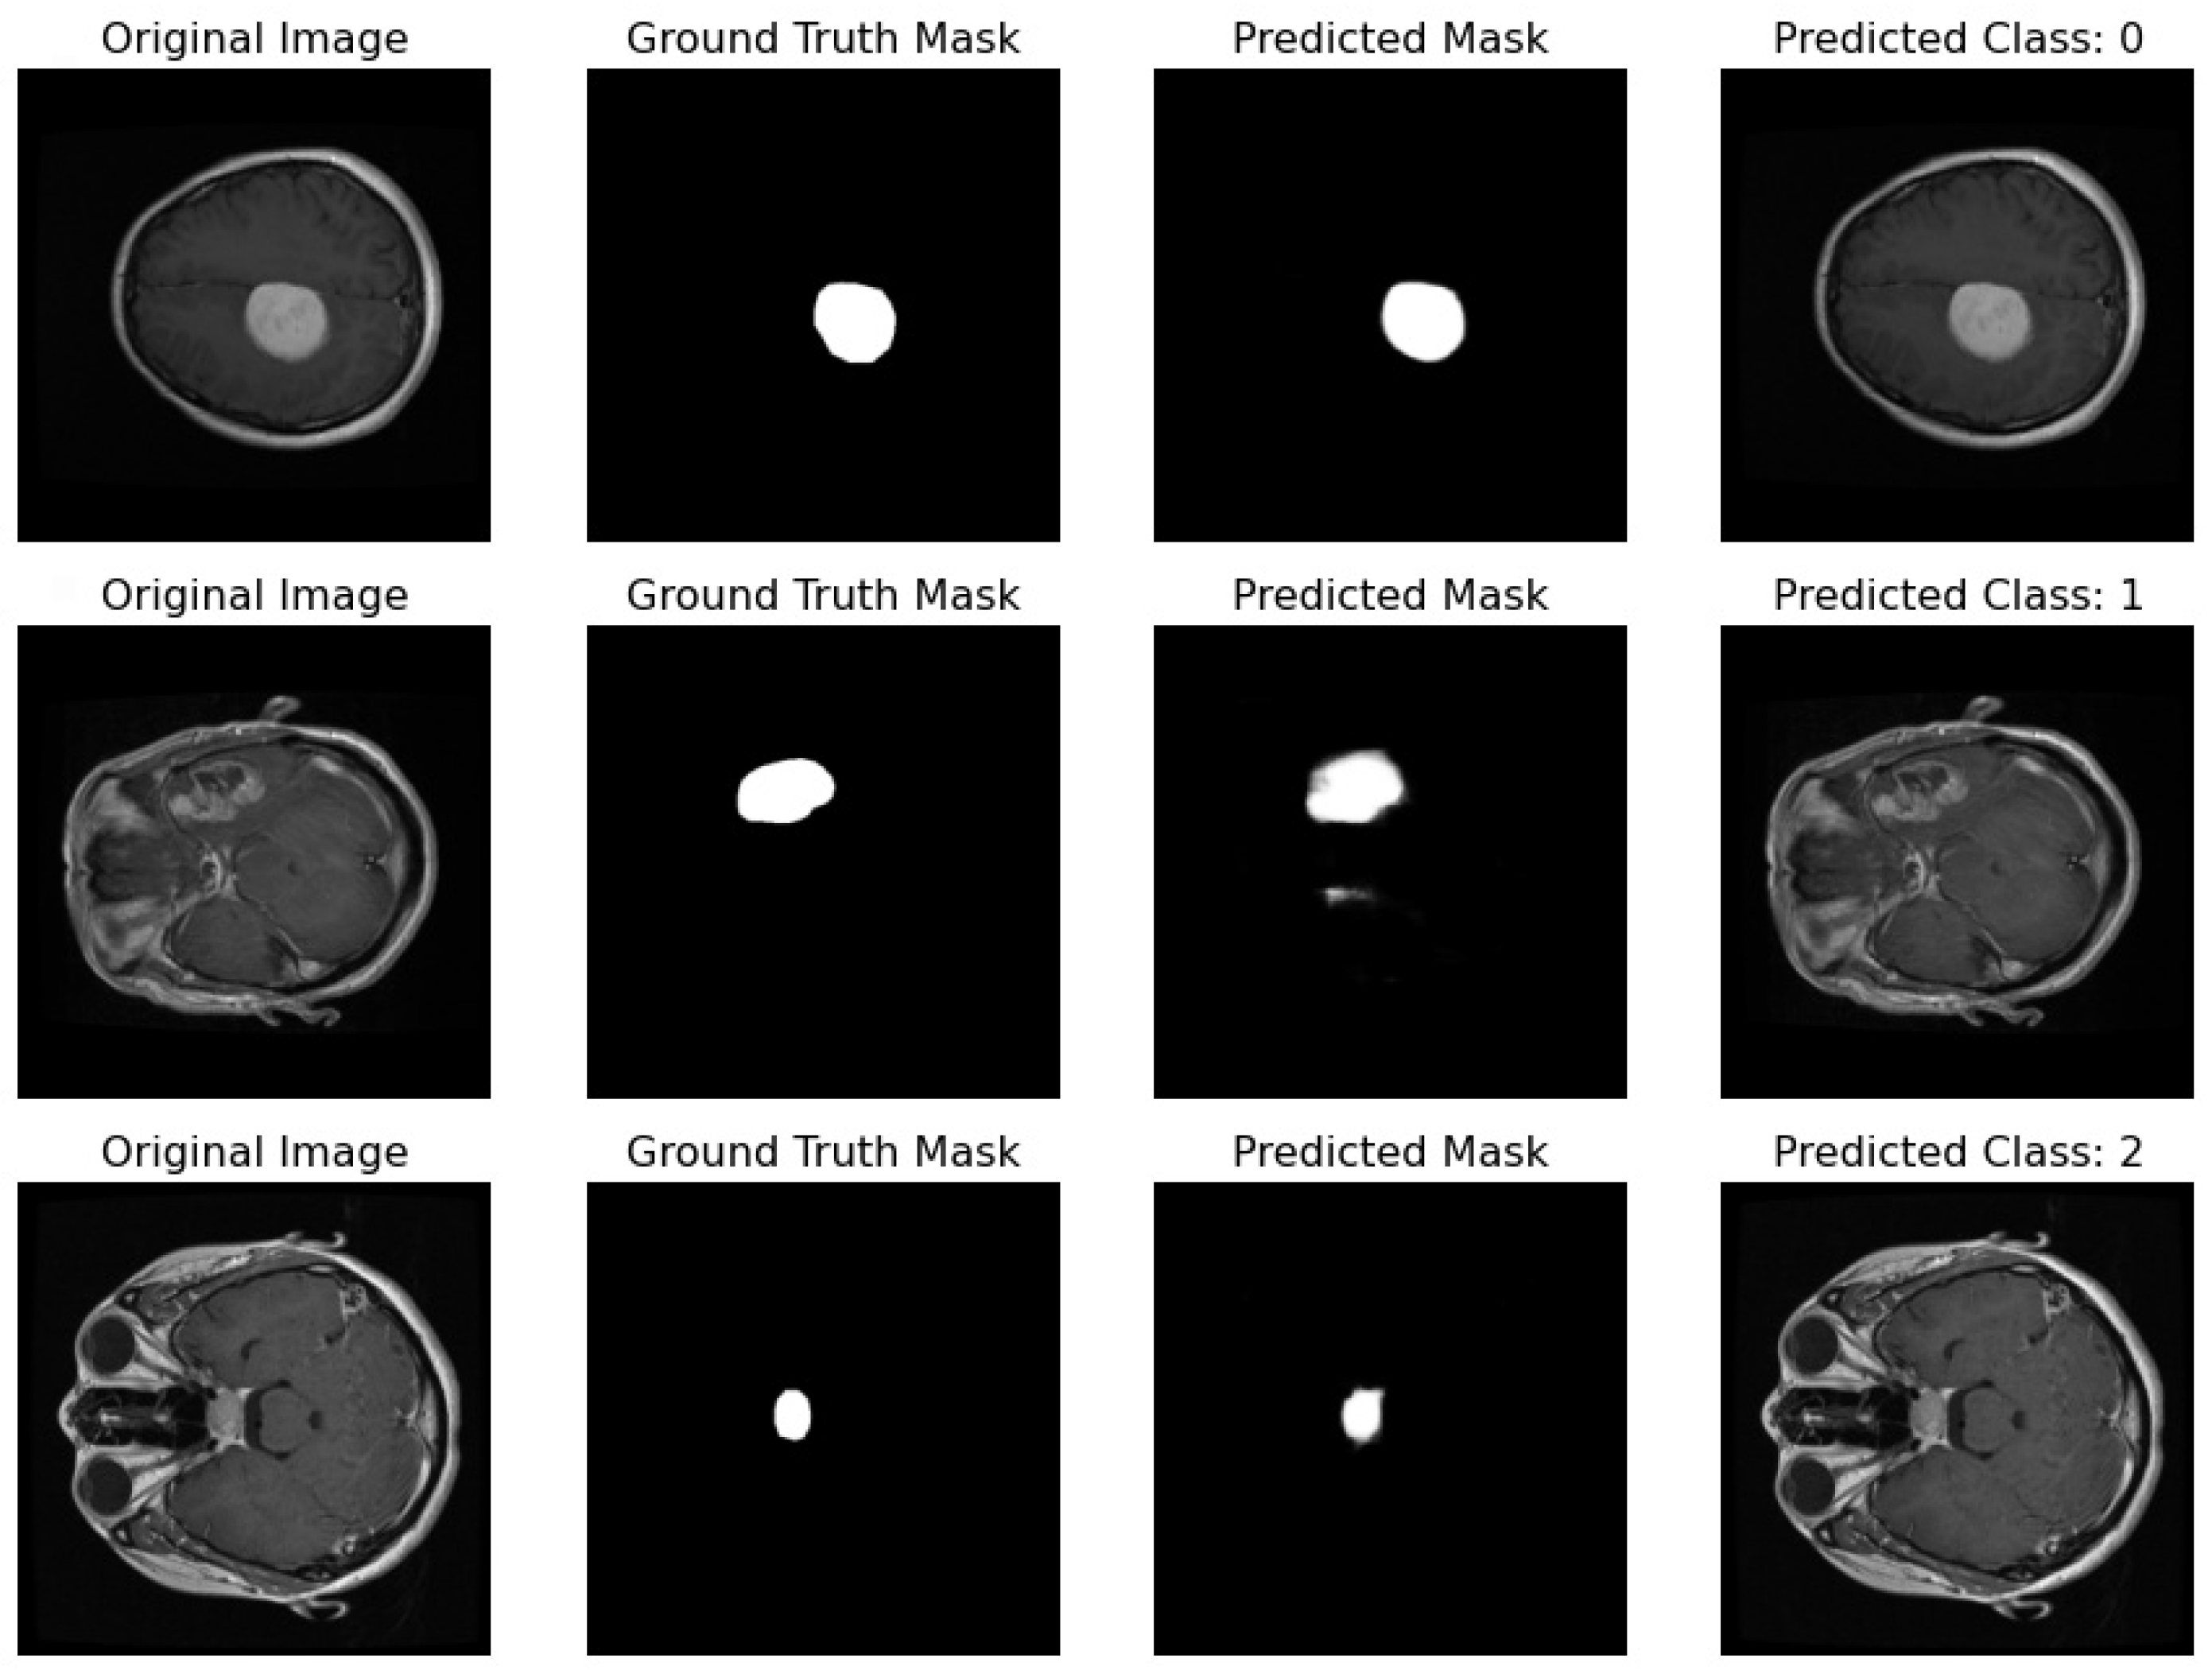

- Original Image: The pipeline receives the MRI scan as its initial input, showcasing a comprehensive cross-sectional view of the patient’s brain and potential pathological features.

- Ground Truth Mask: Next to the original image is the ‘Ground Truth Mask’, meticulously annotated by clinical experts to delineate the regions of clinical significance, such as lesions or tumors.

- Predicted Mask: The segmentation branch of our pipeline then predicts a mask, endeavoring to replicate the expert annotations by encapsulating the region of interest highlighted in the MRI scan.

- Predicted Class: Simultaneously, the classification branch assigns a ‘Predicted Class’ to the scan. The labels, denoted by integers (0, 1, 2), classify the scan into categories that reflect the model’s interpretation of the underlying pathology.